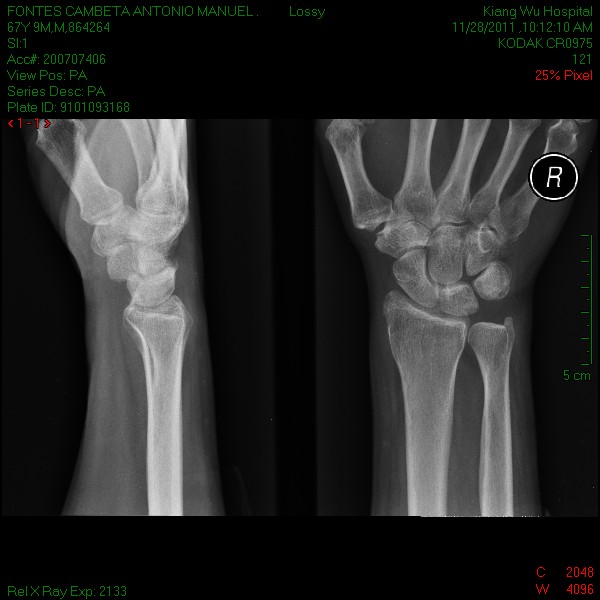

Esta manhã o articulista acordou com imensas dores na mão direita e no ombro esquerdo, os medicamentos que lhe foram receitados, ontem, no Hospital Central Conde de S. Januário não aliviaram em nada as dores, e como só tem consulta marcada para dia 12 de Dezembro, o articulista, telefonicamente marcou uma consulta com o médico Ortopedista no Hospital de Kiang Wu, e após tomar o pequeno almoço seguiu para o referido hospital.

Não demorou muito tempo a ser ocultado pelo médico, tendo o mesmo informado que teria que tirar algumas radiografias para ver o problema mais a fundo.

A mão direita não apresentava qualquer factura, simplesmente, e segundo informção médica, havia um nervo inflamado.

No raioX feito à coluna, aí o problema era bem visível, a quarta vertebra cervical se encontrava como se pode ver, o que necessita de tratamento mais profundo.

Pelas radiografias tiradas o articulista pagou a quantia de 501,00 patacas, cerca de 50 euros.